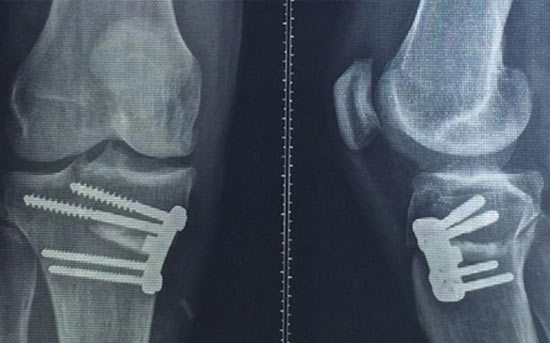

Fotoğraf Başlığı Rivaldo 43 yasinda ilk ameliyatini oldu

Dizinden ameliyat olan 43 yaşındaki futbolcu Rivaldo'nun bacağına vidalar yerleştirildi.

Sağ dizinden geçirdiği sakatlıktan sonra ameliyat olan Rivaldo, bıçak altına yattıktan sonra dizinin son halini paylıştı. Ultrason görüntülerini gösteren yıldız futbolcu dizine vidalar yerleştirildiğini ve bir süre bu vidalarla yaşamak zorunda olacağını açıkladı.